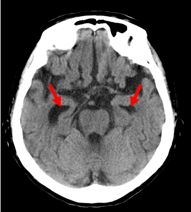

1985年 福島県⽴医科⼤学卒。様々な画像鑑定実績を有し、2011年よりメディカルリサーチ株式会社顧問医として交通事故をはじめとする様々なケースの画像鑑定を行い、交通事故態様、受傷態様から正しい症例把握や症例によって見られる複雑事案についても積極的に取組を展開している。